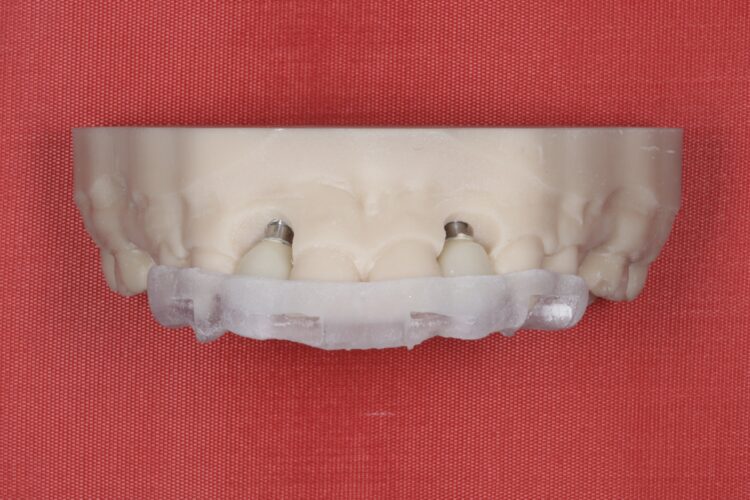

A CBCT scan was taken using a Morita X800. This dataset was imported into the planning software, where it was merged with the STLs of the anatomically correct diagnostic digital wax-up and modules.  With the anatomically correct diagnostic wax-up, there was no ambiguity regarding planning the implant position, angle and depth with precision. I like to plan these types of cases myself, but it is possible to outsource the planning stage for clinicians who are new to the process and looking to increase their workflow efficiency. For this case, I wanted to build up the gingival thickness in order to improve the papillae around the implant sites. The surgical plan, therefore, included soft tissue grafting.

On the day of surgery, a split-thickness envelope flap was raised. Two CONELOG® Progressive-Line implants were placed through the surgical guide in the pre-determined lateral incisor positions. Soft tissue augmentation was performed simultaneously with the implant placement, and the site was sutured and closed without tension. The implants were immediately loaded using provisional crowns that were pre-fabricated in the lab.